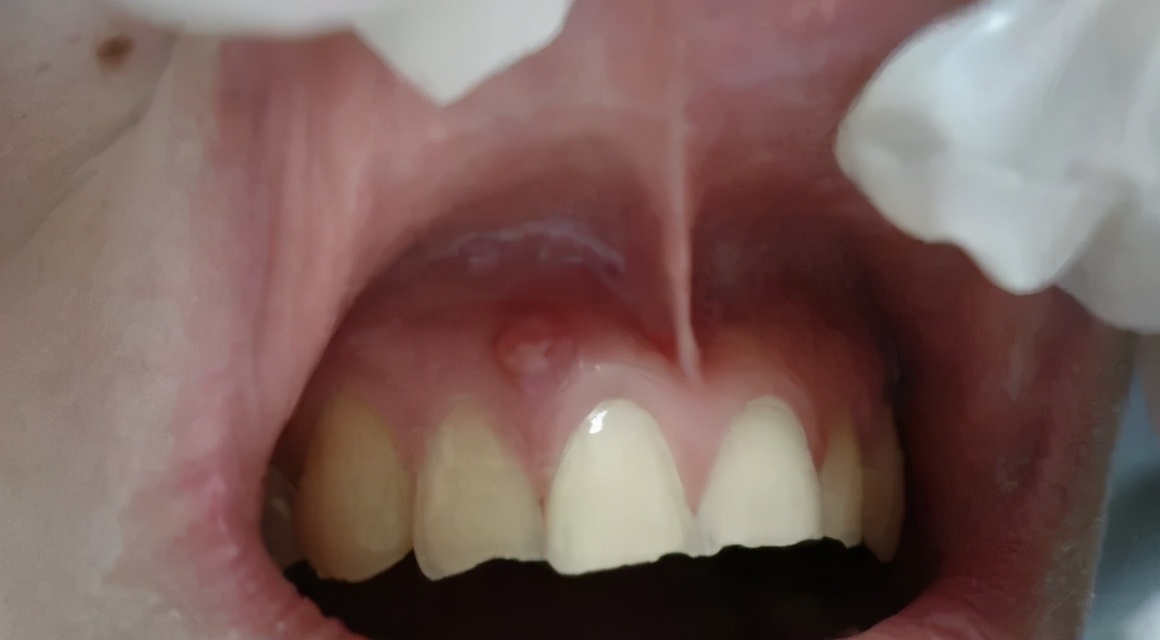

只是个小包包吗?其实并没那么简单!你看到的只是表面现象,长脓包说明牙龈内的牙根已经发炎,细菌感染牙髓演变成牙根炎症,引起牙槽骨蔓延,牙槽骨遭到炎症影响,所以牙龈上才会鼓起一个脓包,从根尖到牙根的瘘管,脓包内产生的分泌物由此流出。而出现这种问题就必须去看牙医了,否则情况就会越来越严重。

当蛀牙蛀到牙髓的时候,细菌感染了牙髓后逐渐繁殖,炎症通过牙髓进而发展大牙根、牙槽骨然后再开始慢慢蔓延,牙槽骨遭到破坏,吸收,便会在牙龈上鼓起一个脓包,形成从根尖到牙根的瘘管,炎症产生的分泌物便由此流出。

如果是由根尖炎症导致的,那么就要拍片检查一下其根尖周组织破坏情况,看看患牙是不是能够保留。如果无法保留,那么就要面临拔除了;如果能够保留,那么就要做牙髓处理(根管治疗),并且在牙龈下做切口排脓,放药,几天后如果好转,就可以做补牙处理了。